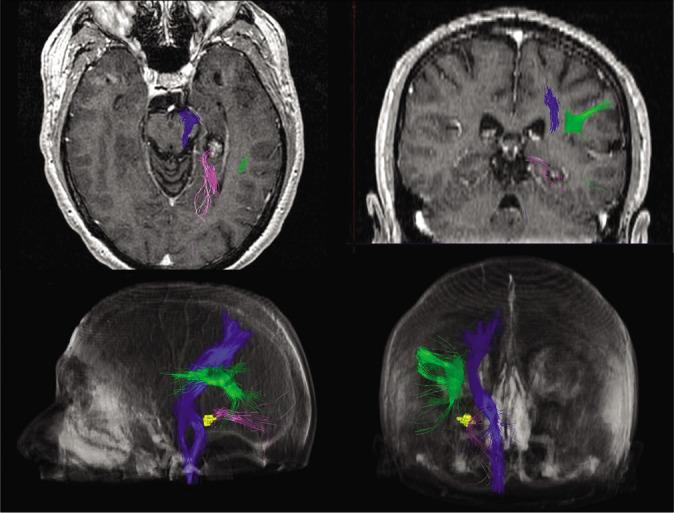

经小脑上幕下入路治疗左侧海马旁海绵状血管畸形

Supracerebellar transtentorial approach for left parahippocampal cavernous malformation.

In this clinical case, it is presented a 56-year-old man with long-term evolution of drug-resistant epilepsy secondary to a cavernoma in the left parahippocampal gyrus. After assessing the lesion, it was decided a SCTT approach for its resection in a semi-sitting position, to avoid language disorders or visual damage. The surgery was uneventful and the patient did not present epileptic seizures during 6-month follow-up.

病例描述